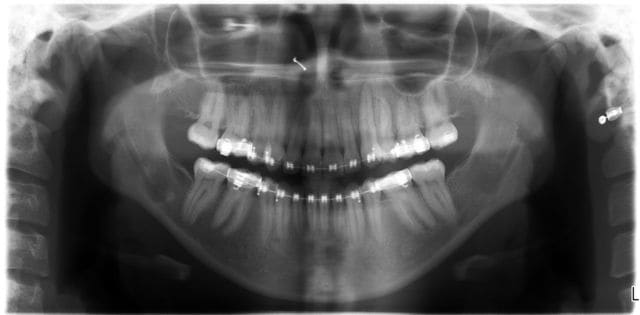

C’est étonnant ce que tu dis, j’ai moi-même toujours utilisé des ligatures métalliques pour tracter les dents incluses et pourtant je n’ai jamais observé de cicatrisations fibreuses ni de labourages de gencive. Je suis orthodontiste qualifié et je m'impose de les dégager moi-même chirurgicalement où qu'elles soient avant de les coller et ce depuis plus de trente ans !

Il m’arrive de temps en temps (très rarement) de coller directement la ligature sur la couronne d’une dent incluse, c’est alors l’extrémité en anneau de son toron que je colle. On a alors les mêmes avantages que tu décris mais on a aussi un inconvénient qui est le manque de liberté qu’on impose à la dent qu’on tracte, et dans les cas où elle est particulièrement loin et où sa venue est acrobatique, cette rigidité peut être un frein à son déplacement.

Comme tu le dis bien, la méthode avec chaînette telle que tu l’exposes n’est utilisable que lorsque la canine est très proche. Lorsque qu’elle est loin et que le placement d’une vis dans le septum n’est pas possible, que fais-tu ?

Dans ces deux cas-ci dont je joins les photos, je ne vois pas très bien comment tu aurais pu faire avec ta méthode. Le premier avait 4 canines incluses, j’ai utilisé un système traditionnel en haut (boutons collés sur les couronnes, ligatures et traction par cantilever) et des ligatures collées directement sur les couronnes et traction par CT8-1 en bas. Pour le second, je me suis servi de l’alvéole déshabitée de la 53 pour passer la ligature, avec un CT8-1. Dans ce dernier cas, où aurais-tu mis ta vis ?

Daniel